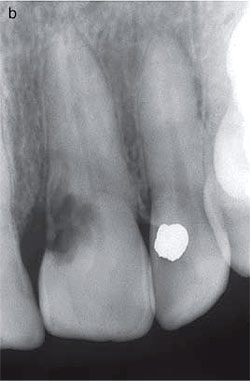

Fig. 18. (a) The maxillary right central incisor of a 21- year-old woman shows

a pink discoloration on the labial aspect of the crown. The tooth had been traumatized

9 years earlier. (b) A radiograph of the maxillary right central incisor reveals

an irregular radiolucency overlying the root canal with no obvious extensions

into the root canal. This invasive cervical resorptive lesion is classified as

Class 2. (c) After a protective application of glycerol to adjacent soft tissue,

The following case reports illustrate this treatment regimen applied to a Class

2 and a Class 3 category invasive cervical resorption. Illustrative Class 2 treatment

A 21-year-old female, with a history of dental trauma showed an invasive cervical

defect in the coronal aspect of her maxillary right central incisor which on

clinicaland radiographic grounds was classified as Class 2 (Figs 18a, b). After

protective application of glycerol toadjacent soft tissues and the placement

of a glycerolimpregnated cotton roll into the labial sulcus, rubber dam was applied

using a cuff technique (Fig. 18c). A small cotton pellet (size 000 divided in

half) which had been dipped into a very small quantity of a 90% aqueous solution

of trichloracetic acid and then dampened on gauze, was applied for 1-2 min with

gentle pressure to the resorptive lesion which was accessible through an enamel

defect near the gingival margin (Fig. 18d). The pressure was slowly increased

as the medicament caused progressive coagulation necrosis of the resorptive tissue

and there was a collapse of the thin overlying enamel (Fig. 18e). The devitalized

avascular tissue was curetted from the resorption cavity, which was then carefully

checked under magnification with an enhanced light source. This examination revealed

an intact smooth dentine floor cavity with no communication with the dental pulp

(Fig. 18f). The cavity margins were then smoothed with a high-speed tungsten

carbide bur under water spray and the defect restored with a glassionomer cement,

protected with a light-activated unfilled bonding resin (Fig. 18g). Follow-up

examinations to 5 years did not reveal any evidence of pulpal or periapical pathology

or continuation of the resorptive process, and the restoration and adjacent gingival

tissues were assessed as most satisfactory (Figs 18h, i). If there had been obvious

pulp involvement on removal of the resorptive tissue, pulpectomy would have been

carried out accessing the canal via the resorption cavity to retain as much residual

tooth structure as possible. A similar treatment regimen to the illustrative

Class 2 case shown above can be applied to a Class1 category of invasive cervical

resorption.